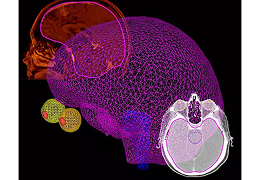

• Pinnacle³ 9.8

现在,剂量计算速度在治疗计划过程发挥着越来越重要的作用...

计划软件